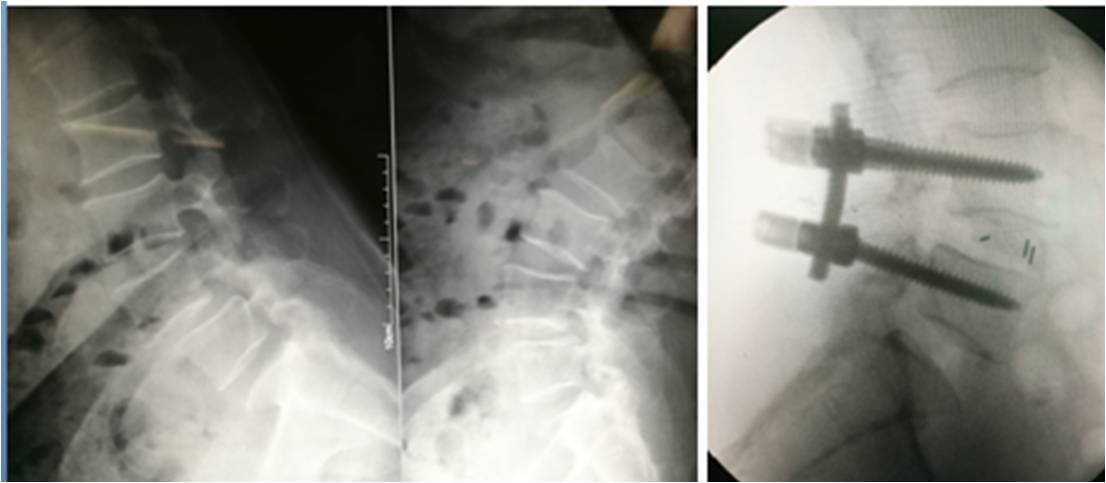

胸椎及腰椎骨折的治療